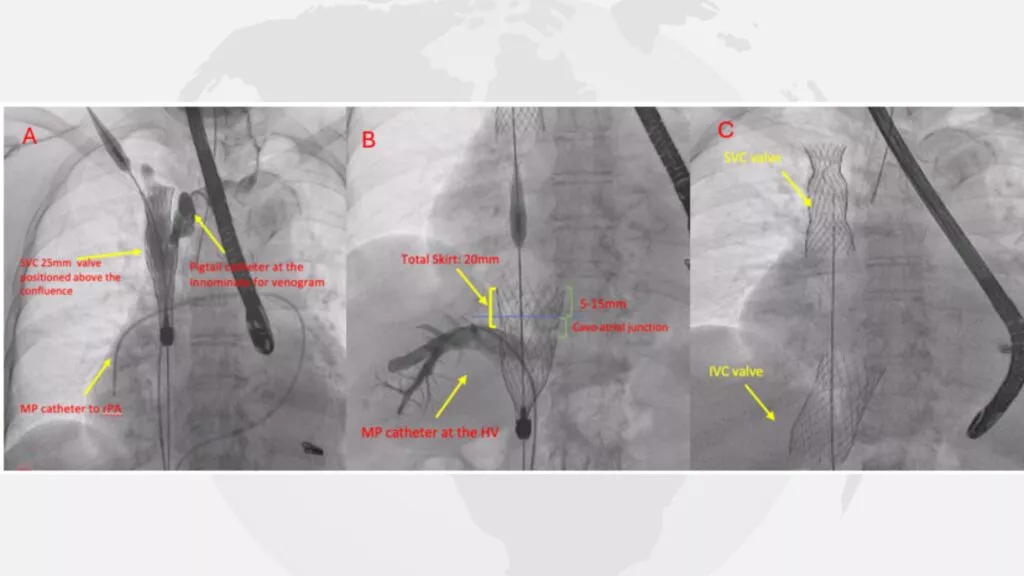

Given the severity of symptoms and the patient’s ineligibility for surgery, heterotopic heart valve replacement with CAVI (Caval Valve Implantation) with TricValve was selected. The procedure was successfully performed on 3 April 2024.

Despite prior therapy, her tricuspid regurgitation progressed, presenting with worsening abdominal bloating, prominent neck vein distention, bilateral pedal edema, and severe hepatic venous congestion. Diagnostic evaluation revealed a coaptation gap of 7 mm, TAPSE of 23 mm, FAC of 41%, sPAP of 55 mmHg, and elevated caval and right atrial v-waves. Risk assessment indicated high surgical risk (STS 7.39%, EuroSCORE 3.86, TRI-Score 4/12) with an NT-proBNP level of 3,297 ng/mL.